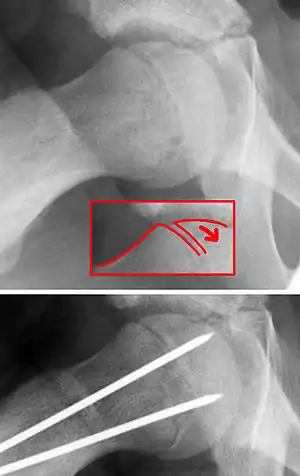

| X-ray showing a slipped capital femoral epiphysis, before and after surgical fixation. | |

Once SCFE is suspected, the patient should be non-weight bearing and remain on strict bed rest. In severe cases, after enough rest the patient may require physical therapy to regain strength and movement back to the leg. A SCFE is an orthopaedic emergency, as further slippage may result in occlusion of the blood supply and avascular necrosis (risk of 25 percent). Almost all cases require surgery, which usually involves the placement of one or two pins into the femoral head to prevent further slippage.[13] The recommended screw placement is in the center of the epiphysis and perpendicular to the physis.[14] Chances of a slippage occurring in the other hip are 20 percent within 18 months of diagnosis of the first slippage and consequently the opposite unaffected femur may also require pinning.

The risk of reducing this fracture includes the disruption of the blood supply to the bone. It has been shown in the past that attempts to correct the slippage by moving the head back into its correct position can cause the bone to die. Therefore the head of the femur is usually pinned 'as is'. A small incision is made in the outer side of the upper thigh and metal pins are placed through the femoral neck and into the head of the femur. A dressing covers the wound.